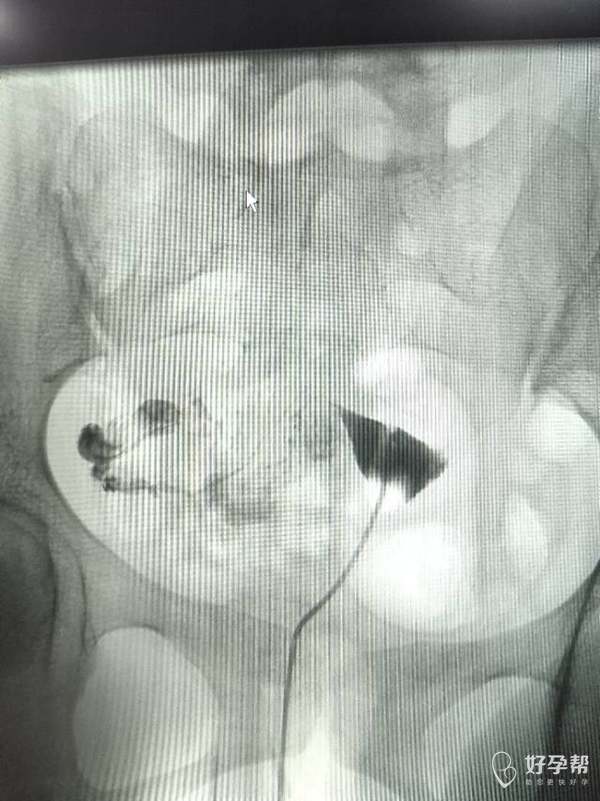

两侧输卵管堵试管成功率高吗

回答

输卵管堵塞,是试管的指征,成功率都挺高的